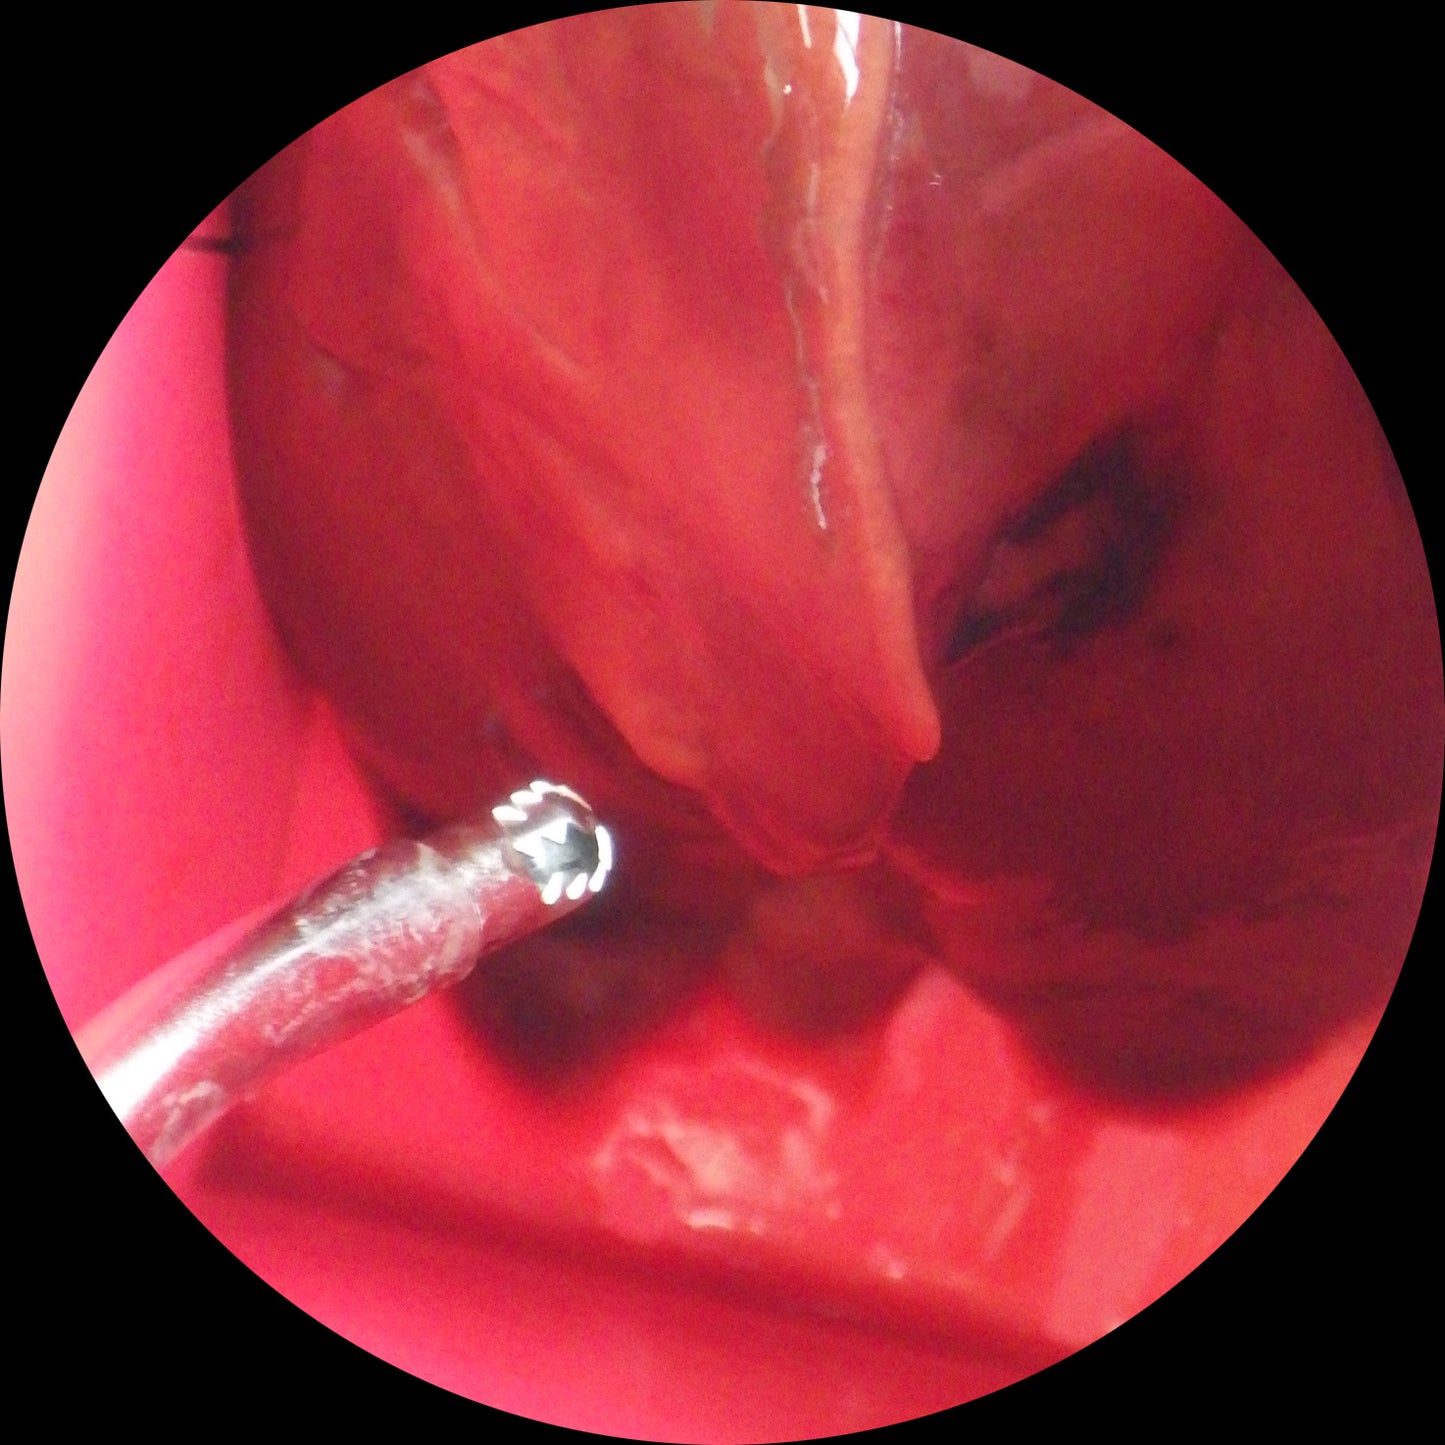

ESSトレーニングモデル

デブリッターのトレーニングBOX(1セット6個入り)

鼻副鼻腔内での正確な操作を目的とした訓練に役立ちます。

パプリカなどを使用したトレーニングの準備を簡素化できます。

大村和弘先生による効果的な練習動画をあわせてご活用ください。

トレーニングBOXの練習動画をご提供トレーニングBOXを購入いただいた方には、NPO法人 KnotAsia 代表の大村和弘医師監修によるトレーニングキットの練習動画をご提供します。 |